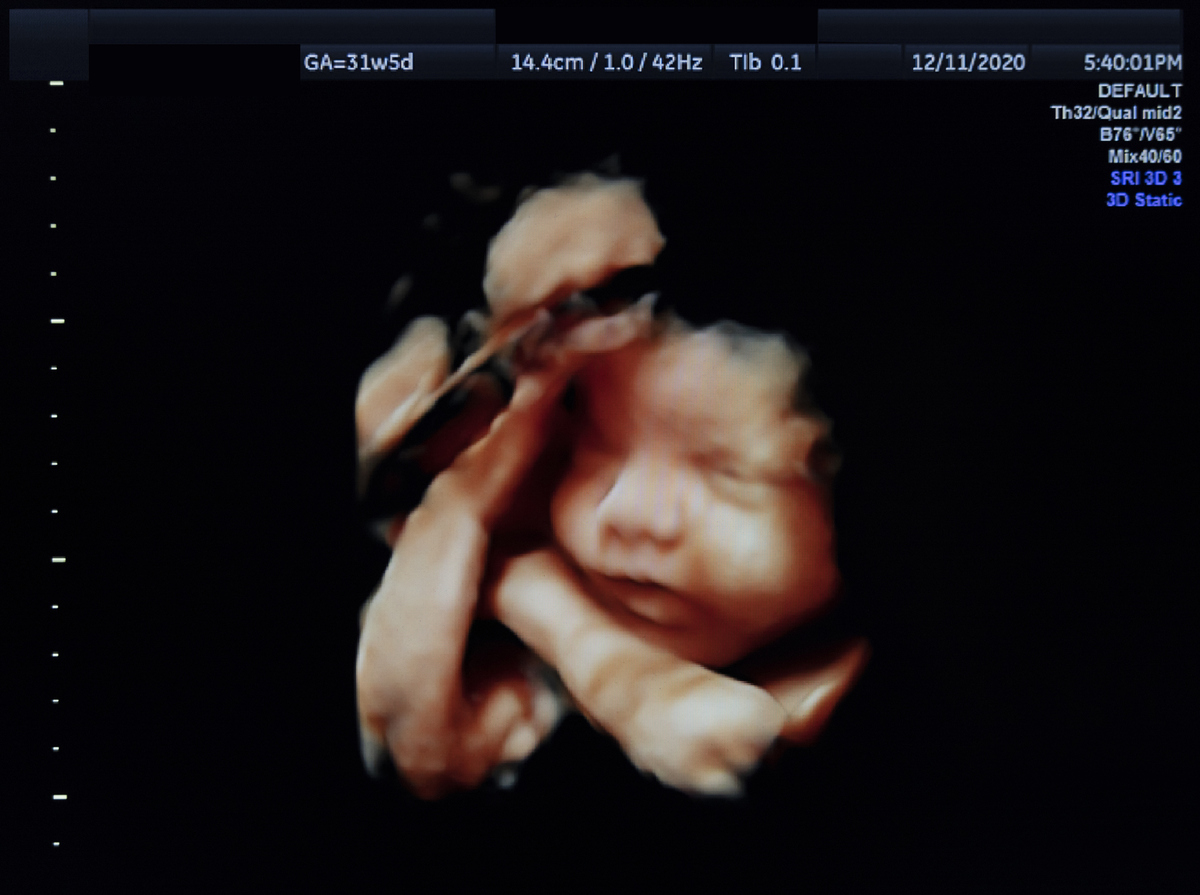

Εξοικειώνεται επίσης και με νέες ορολογίες, με το γλωσσάρι που θα κυριαρχήσει στην επικοινωνία με τον ειδικό γιατρό: «ολιγοασθενοσπερμία», «ωοληψία», «εμβρυομεταφορά», «ωοθηκική διέγερση», όλα όσα περιγράφουν μια επιστημονική περιπέτεια που ξεκίνησε σαράντα τέσσερα χρόνια πριν, όταν γεννήθηκε το πρώτο «παιδί του σωλήνα».

Στις 27 Ιουλίου 1978, η βρετανική εφημερίδα Evening News έχει πρωτοσέλιδο το «super babe»: Τη βρετανίδα Λουίζ Μπράουν, το πρώτο παιδί που πριν από δύο μέρες είχε έρθει στον κόσμο με εξωσωματική γονιμοποίηση, φέρνοντας δάκρυα στα μάτια της μητέρας του, της Λέσλι. Εκείνη και ο άντρας της, Τζον, προσπαθούσαν εννέα ολόκληρα χρόνια να κάνουν παιδί, μέχρι που αποδέχτηκαν την πρόταση του καθηγητή Ρόμπερτ Έντουαρντς και ξεκίνησαν την πρωτοφανή για την εποχή διαδικασία. Έκτοτε, έχουν έρθει στον κόσμο περισσότερα από 8 εκατομμύρια παιδιά με IVF (In Vitro Fertilization), που επί λέξει σημαίνει «γονιμοποίηση στο γυαλί», δηλαδή σε δοκιμαστικό σωλήνα.